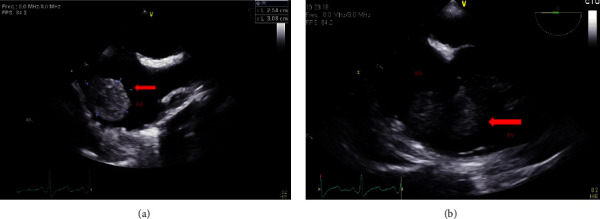

约有 4%-10% 的肾细胞癌(RCC)患者有肿瘤血管侵犯,导致肾静脉和下腔静脉(IVC)出现血栓。作者描述了一例有趣的病例,在 RCC 切除术中,IVC 肿瘤血栓移至右心腔。术中经食道超声心动图(TEE)显示右心房(RA)和右心室(RV)之间存在自由漂浮的血栓,从而做出了诊断。在完成肾切除术之前,患者需要进行紧急胸骨切开术,并使用心肺旁路术(CPB)清除心房血栓。患者完全康复并出院前往康复机构。这些发现说明了在肾切除术和输尿管血栓切除术中进行术中 TEE 监测的重要性。在该病例中,通过 TEE 诊断出了意想不到的并发症,需要及时进行心脏手术治疗。

Approximately 4%-10% of patients with renal cell carcinoma (RCC) have tumoral vascular invasion with resultant thrombi in the renal vein and in the inferior vena cava (IVC). The authors describe an interesting case of IVC tumor thrombus that migrated to the right cardiac chambers during RCC resection. The diagnosis was made by intraoperative transesophageal echocardiography (TEE), which revealed the presence of a free-floating thrombus between the right atrium (RA) and right ventricle (RV). The patient required an urgent sternotomy with cardiopulmonary bypass (CPB) for atrial thrombus removal prior to the completion of the nephrectomy. The patient made a full recovery and was discharged to a rehabilitation facility. These findings illustrate the importance of intraoperative TEE monitoring during nephrectomy and IVC thrombectomy. In this case, TEE allowed for the diagnosis of an unexpected complication necessitating prompt cardiac surgical management.